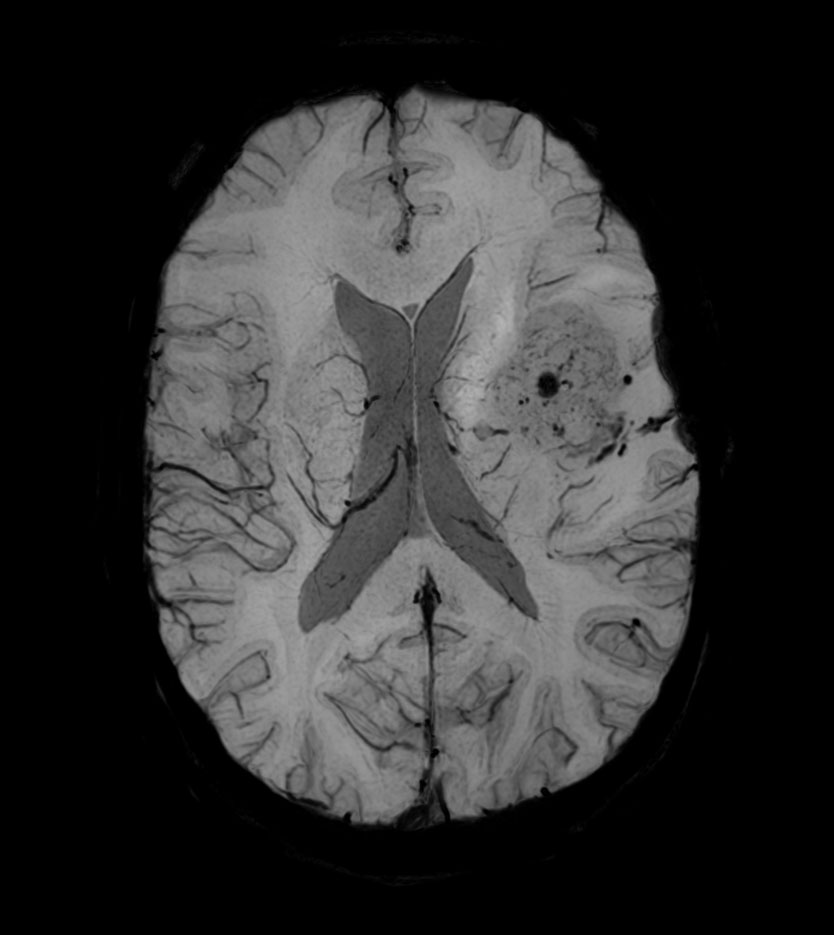

Axial SWIp